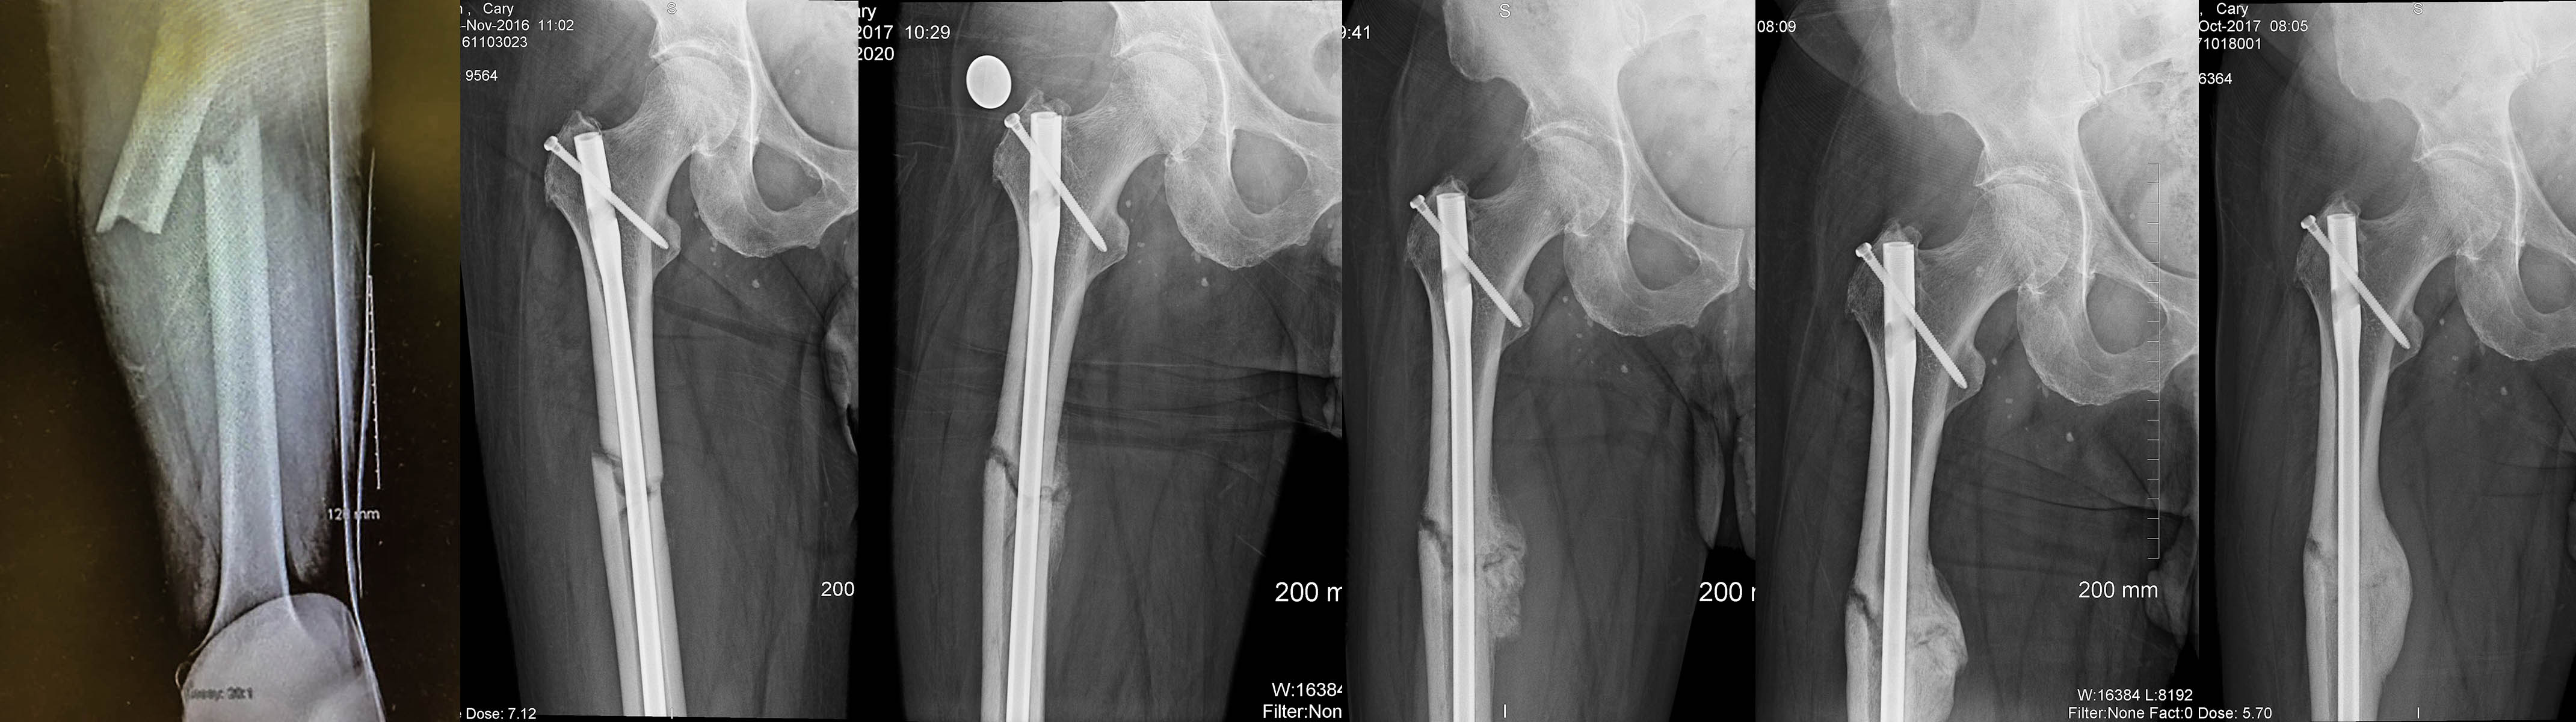

A friend offered a friendly ride on a borrowed mtn bike last week – the brakes failed on downhill, I bailed off and tumbled, and cleanly broke my right femur. It didn’t penetrate the skin, nor (most importantly) cut my femeral artery. Pure luck.

I was in the ER in Santa Fe by 6:00PM – they did surgery ASAP: aligned the bones, drilled out the core, and installed an internal continuous rod, screwed everything together and stapled me up! I was in my room by 3AM.

Four days in hospital (St Vincent Med Center), now five days at home, healing nicely. Thanks for your interest – here are a few pics: